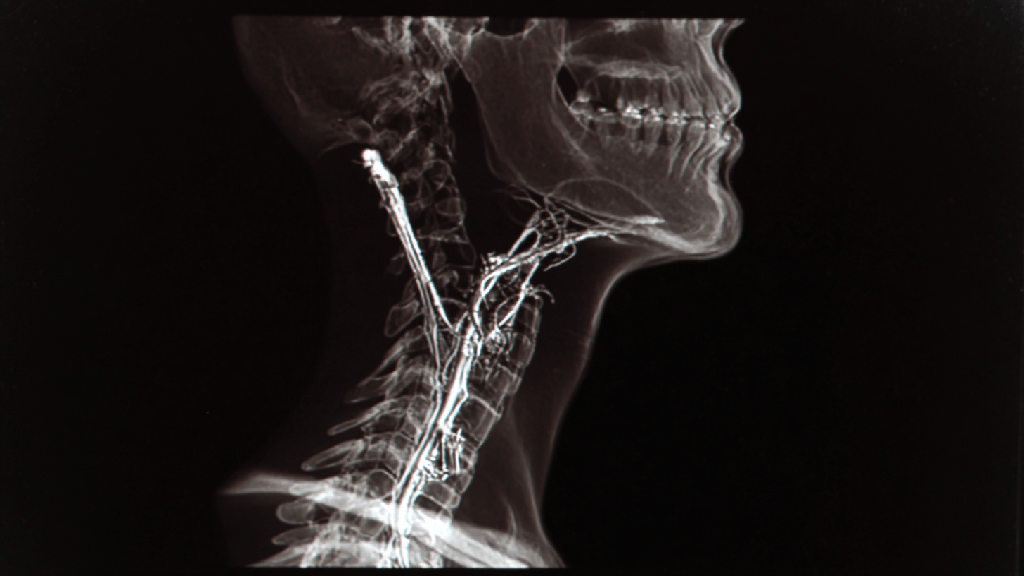

- Рентгенография пищевода с барием — классический метод, позволяющий выявить задержку бариевой взвеси, расширение пищевода.

- КТ или МРТ органов грудной клетки — применяются при подозрении на вторичную (псевдо) ахалазию.